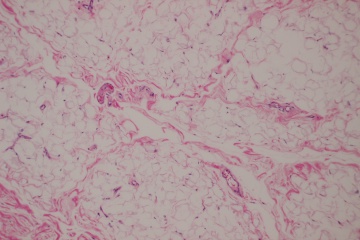

The underlying pathology has not been studied extensively for this disease process. However, several case reports have demonstrated distinct findings in the affected eyelid tissues at the cellular level supporting an underlying immunopathogenic process. Eyelid biopsy in a single patient with blepharochalasis revealed perivascular and interstitial infiltration of lymphocytes in the dermis associated with a marked decrease in elastic fibers. Staining of MMP-3 and MMP-9 was detected in and around infiltrating cells in the dermis. [3] In another study, abundant IgA deposits surrounding atrophic elastic fibers in the eyelid skin of a patient was reported, while these deposits were absent in a control sample of a remote skin biopsy site. [4]